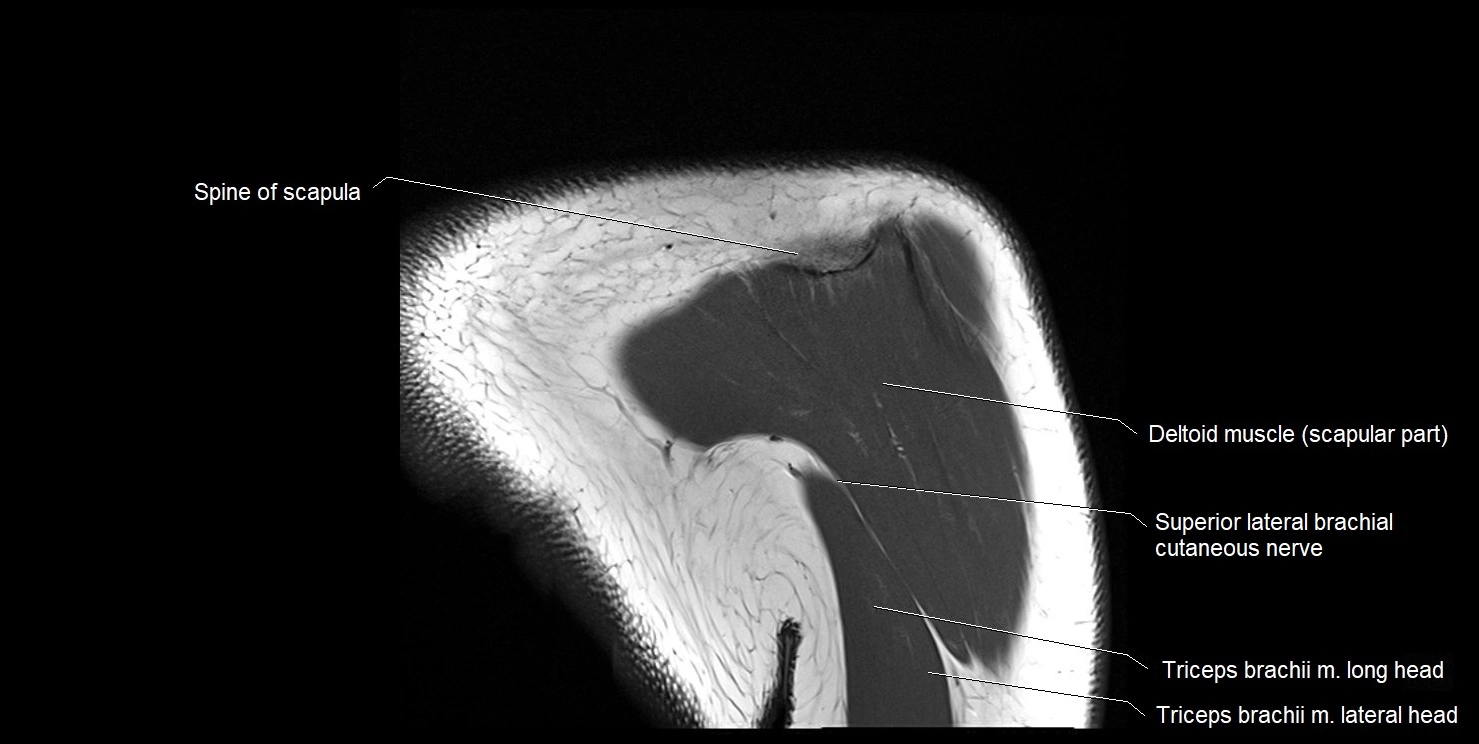

MRI images

image